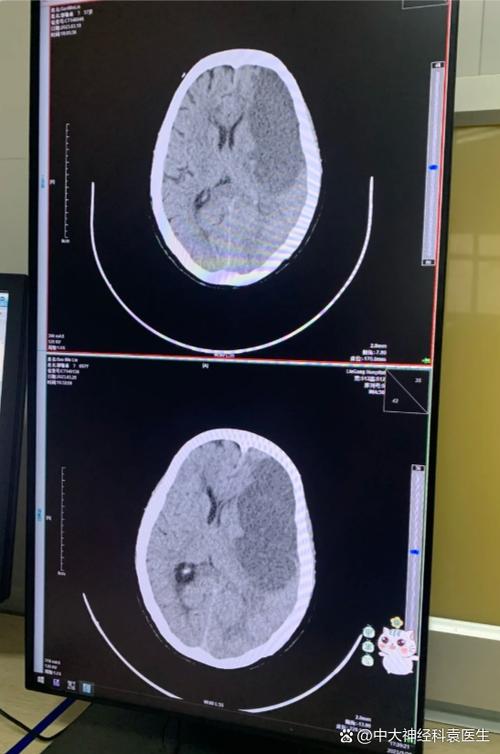

(图片来源网络,侵删)